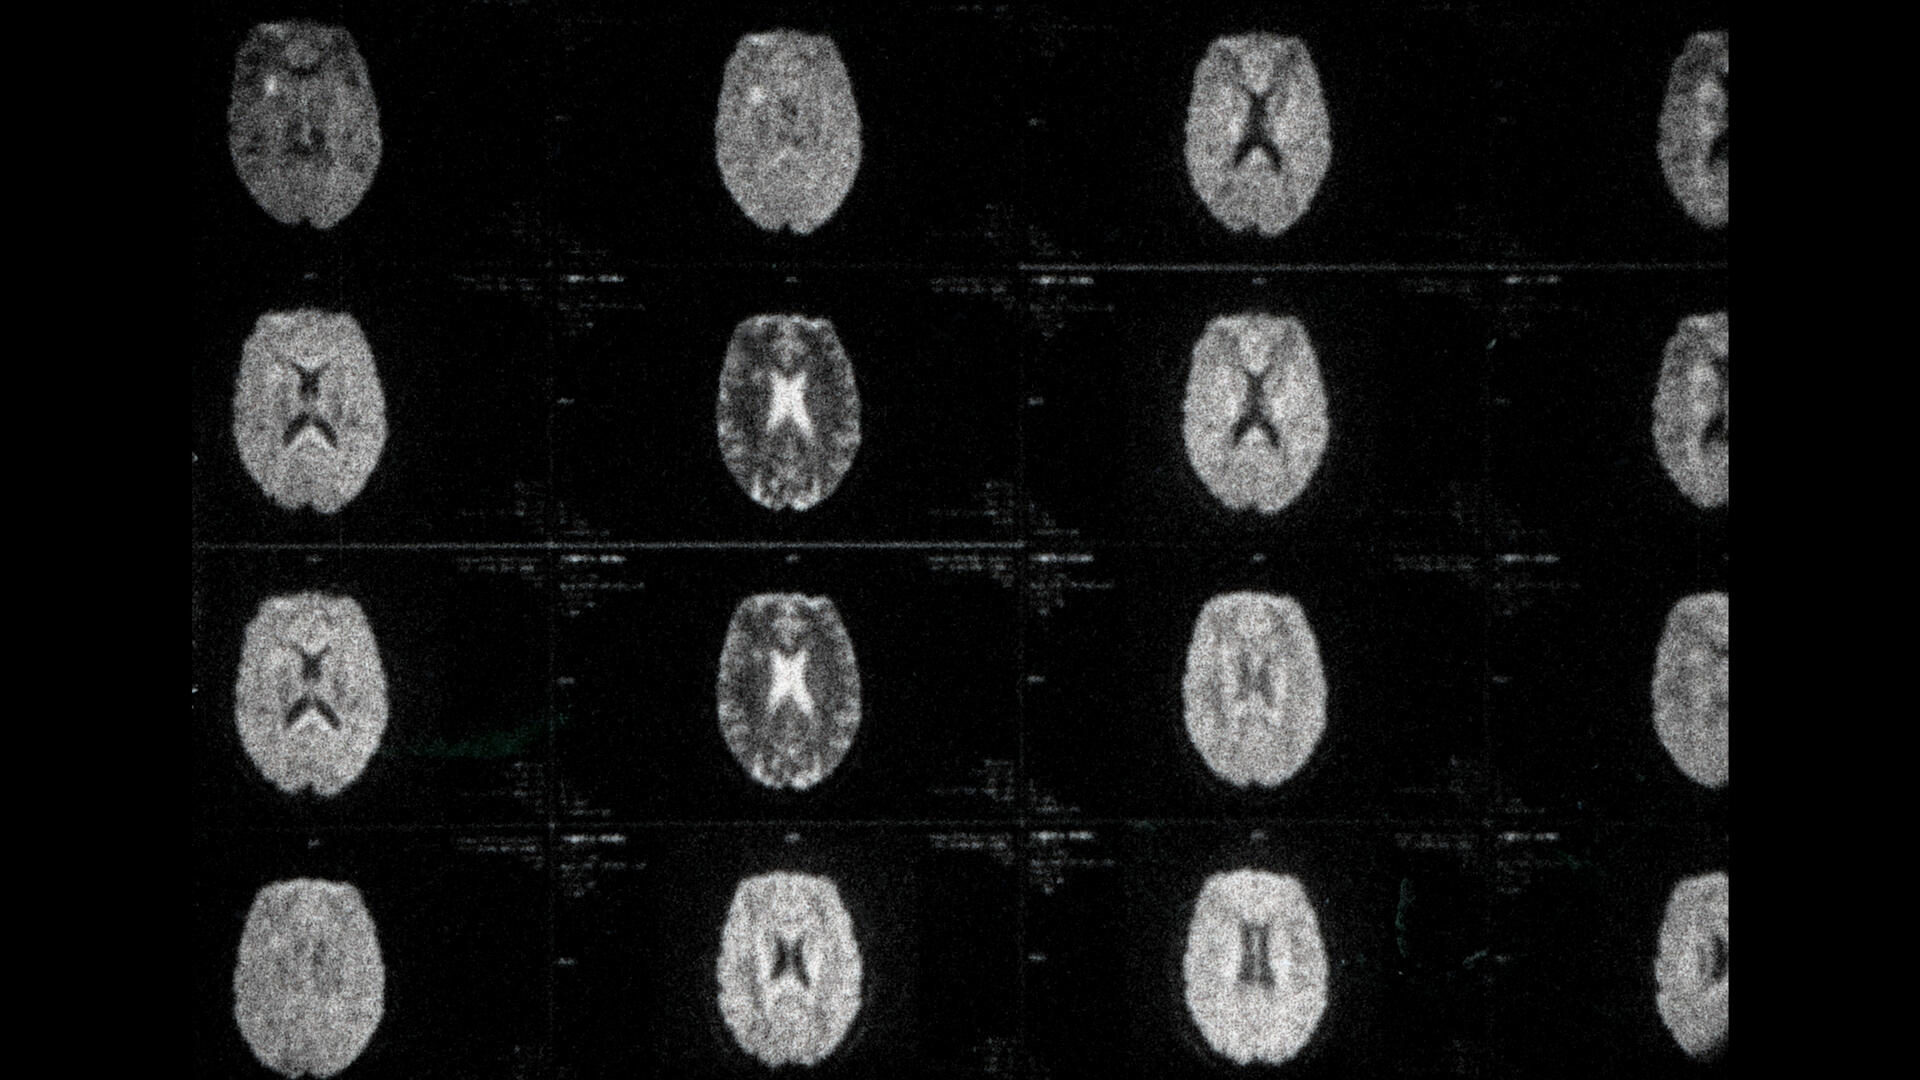

In My Head is an experimental first-person short film about the filmmaker’s multiple sclerosis as told through magnetic resonance images. This film-journal traces the ebb and flow of life that persists through illness.

Abstraction, Cinema, Identity, Illness, Portrait, Psychology, Health, Mental Health